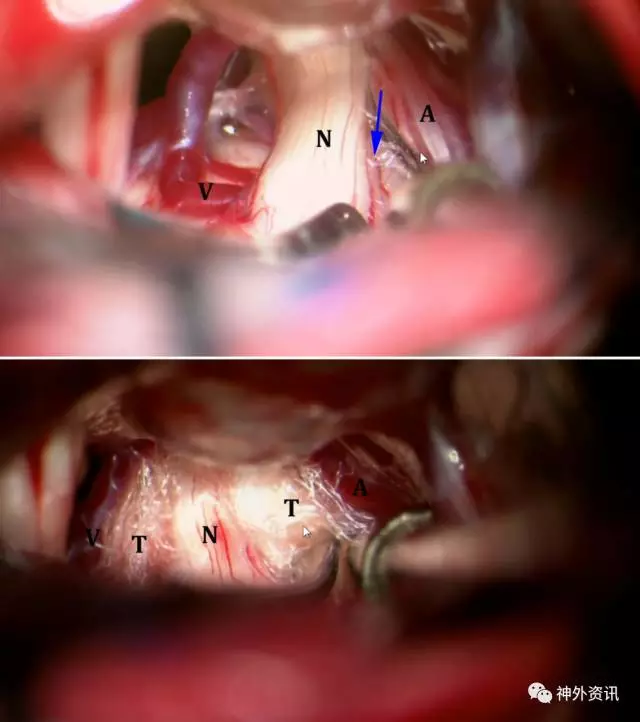

图8. 小心切开蛛网膜和正确地辨别神经很关键。注意保留脑干周围的血管。分离深部的蛛网膜应谨慎,首先用球头剥离子分离缠绕的血管(上图)。三叉神经比面听神经复合体位置更深、更靠近内侧。面听神经复合体位置则相对表浅,斜向下或向上走行,不要误认为是三叉神经(下图)。

图14. 左侧乙状窦后入路典型的神经血管压迫:蓝色箭头指示神经受压位置(N)。动脉(A)以及潜在的责任静脉(V)用Teflon棉隔开。

神经血管接触的变异

图16. 微血管减压术术中照片:通常有多条责任动脉(A)和责任静脉(V),上一条责任动脉隐藏在三叉神经运动根(MR)后方(左上图和右上图)。使用Teflon棉可以完整地隔开侵犯的动静脉袢(左中图)。过度增生的岩骨隐藏了血管袢(右中图)。通过磨平过度增生的岩骨,可显露出之前隐藏的血管袢(左下图)。静脉袢也可能是血管压迫的唯一来源(右下图)。